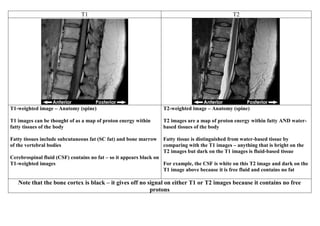

T1-weighted image – Anatomy (spine)

T1 images can be thought of as a map of proton energy within

fatty tissues of the body

Fatty tissues include subcutaneous fat (SC fat) and bone marrow

of the vertebral bodies

Cerebrospinal fluid (CSF) contains no fat – so it appears black on

T1-weighted images

T2-weighted image – Anatomy (spine)

T2 images are a map of proton energy within fatty AND water-

based tissues of the body

Fatty tissue is distinguished from water-based tissue by

comparing with the T1 images – anything that is bright on the

T2 images but dark on the T1 images is fluid-based tissue

For example, the CSF is white on this T2 image and dark on the

T1 image above because it is free fluid and contains no fat

Note that the bone cortex is black – it gives off no signal on either T1 or T2 images because it contains no free

protons